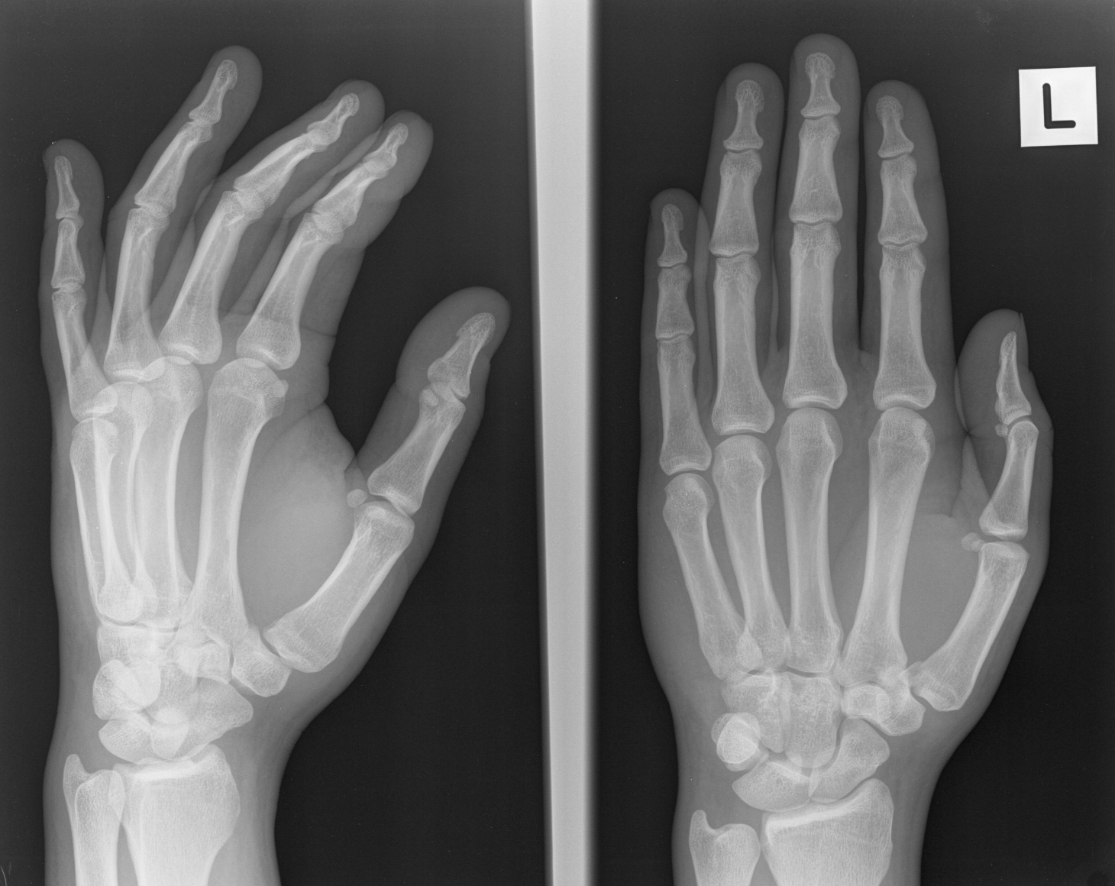

found a fracture on my left thumb at the base of the bone right where the socket / joint is,

on the inner side of the thumb facing my left index finger i think .